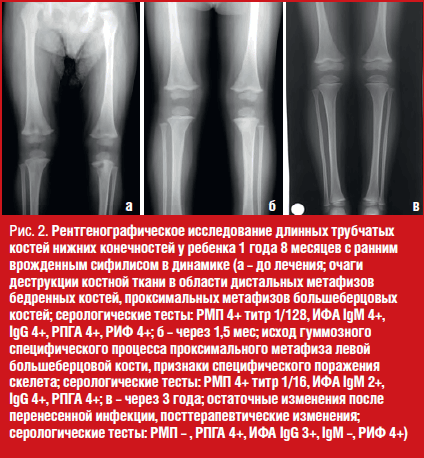

Результаты серологического обследования ребенка при госпитализации: РМП + 1/128, ИФА IgM 4+, IgG 4+, РНГА 4+, РИФ 4+. Данные рентгенографии бедренных костей и голеней: очаги деструкции костной ткани (гуммы) в области дистальных метафизов бедренных костей, проксимальных метафизов большеберцовых костей (рис. 2а).

Через две недели был проведен второй курс в течение 10 дней. При поступлении? состояние ребенка удовлетворительное, жалоб нет. Наблюдалась положительная динамика серологических показателей крови ребенка со снижением титров РМП в 8 раз, позитивности ИФА IgM – в 2 раза. Заключение рентгенографического исследования длинных трубчатых костей нижних конечностей через 6 недель: «Исход гуммозного специфического процесса проксимального метафиза левой большеберцовой кости. Признаки специфического поражения скелета. Положительная динамика от первичной рентгенограммы» (рис. 2б).

По данным клинико-лабораторного наблюдения полный регресс специфических изменений со стороны костной системы произошел через 6 месяцев (по данным рентгенографического исследования), негативация нетрепонемных тестов – через 2 года.